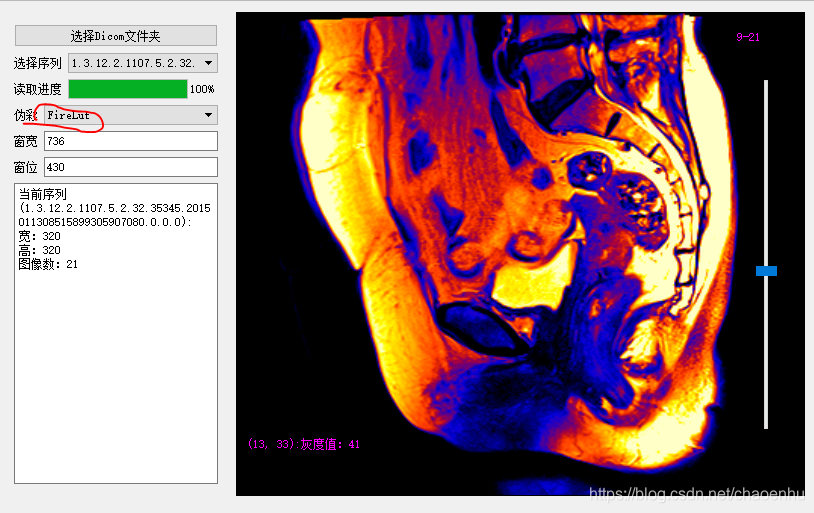

...运行调试,点击“选择Dicom文件夹”后

设置伪彩色

调整窗宽窗位:1)通过按住拖动鼠标右键;2) 修改窗宽窗位值;3) 按住鼠标左键划框(感兴趣区域);